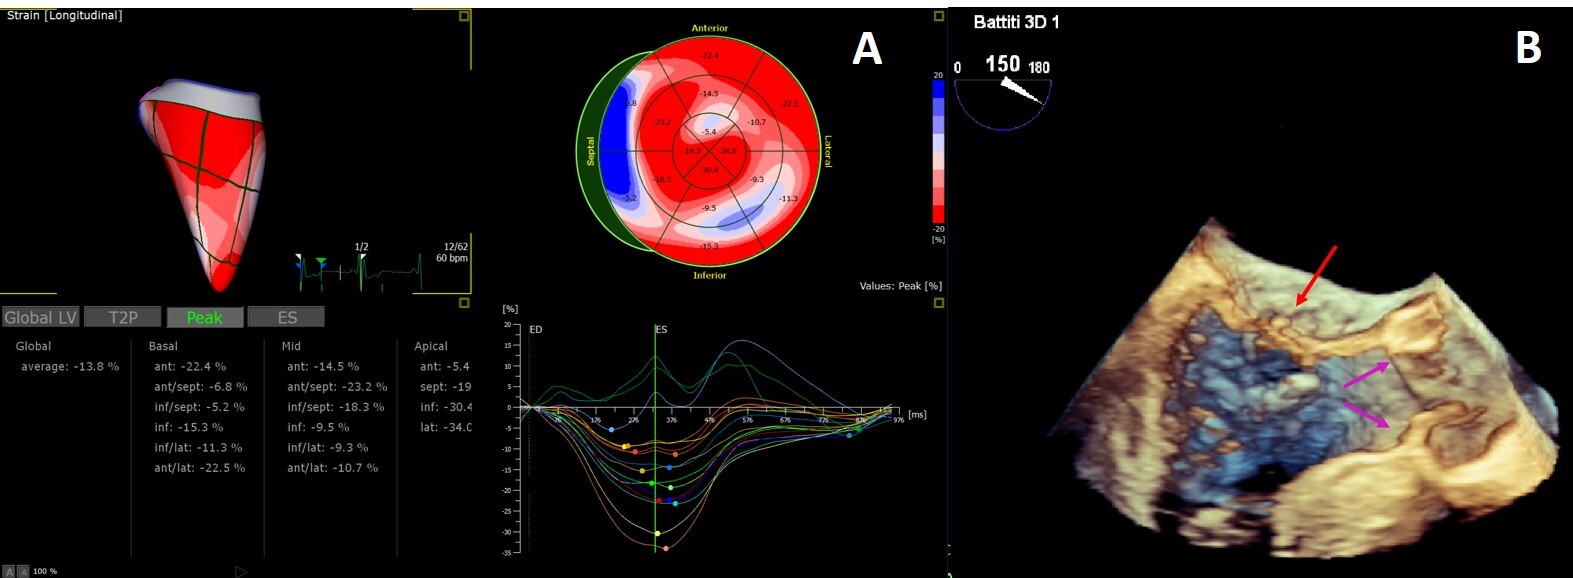

The added value of 3D echocardiography needs to be proved but its strong correlation with CMR for the estimation of LVM and LVEF [103, 104] and for the detailed study of myocardial strain [105, 106] and heart valves [77] (Fig. 5) is promising.

Fig. 5.3D Echocardiography. (A) 3D echocardiography LV-analysis with regional strain analysis mapped onto the LV model and shown in the bull’s eye plot for clear visualization. (B) 3D transesophageal echocardiogram mid-esophageal long axis view. The arrow points to minor chordal rupture and the purple arrows to mild aortic cusps thickening.